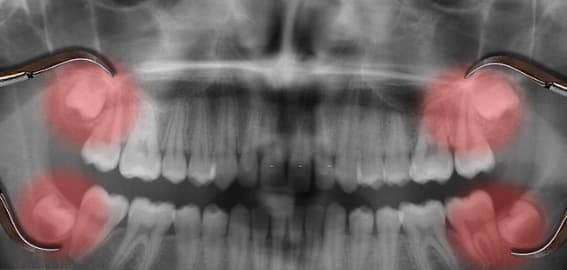

– Răng khôn là những răng mọc ở cuối hàm, thường phát triển khi cung hàm đã phát triển đủ răng.

– Theo nghiên cứu, răng khôn hàm dưới có tỷ lệ mọc ngầm và mọc lệch lớn hơn răng khôn hàm trên.

Răng khôn thường mọc lên trong giai đoạn trưởng thành, khoảng 18 – 25 tuổi